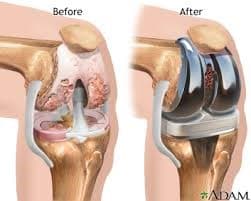

Өвдөгний үе бүтэн солих мэс засал (TKA) image2

Эгц урдаас

Хажуугаас

Рентген, эгц урдаас харуулсан байдал

Рентген, хажуугаас харуулсан байдал